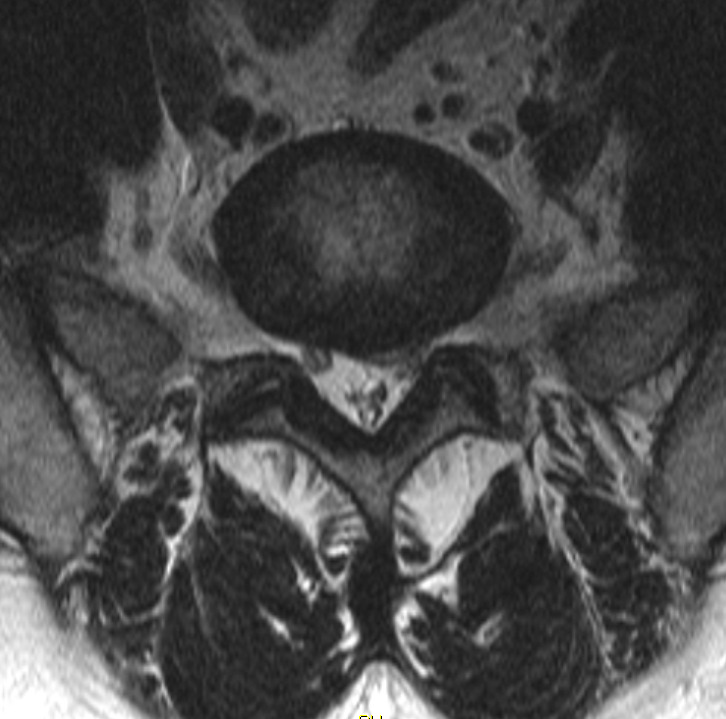

둘째, 허리디스크의 예후는 척추관(vertebral canal) 크기와 디스크 탈출 정도(Barrel and Contents mechanism)와 관련이 있습니다. 즉 척추관(vertebral canal) 형태가 작고, 아래 그림과 같이 클로버잎(trefoil shape) 형태인 경우에는 디스크가 약간만 탈출돼도 신경근(nerve root)이 심하게 압박되어 심한 통증과 근위약, 근위축 등 심각한 증상이 나타날 수 있습니다.

이것은 컴퓨터단층촬영(CT), 자기공명영상(MRI) 축(axial)사진으로 쉽게 확인할 수 있습니다. 반대로 척추관이 넓으면 디스크 탈출이 심해도 신경근(nerve root) 압박은 미미하여 통증이 가볍고 신경학적 증상도 가벼울 수 있습니다. 특히 급성 허리디스크 환자에서는 척추관 크기와 디스크 탈출 정도에 따른 예후 판단과 신경학적 검진에 의한 예후판단이 매우 중요합니다.

그림. trefoil shape 척추관과 디스크 탈출 사진

그림. 넓은 척추관과 디스크 탈출사진